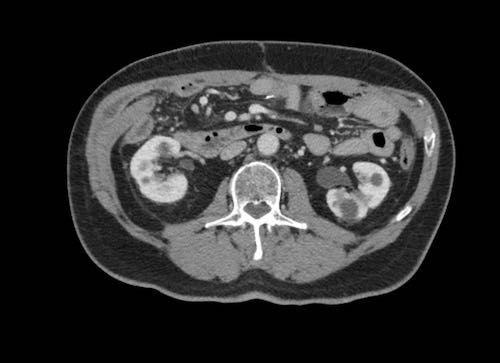

Cuộn xem ảnh CT

Ca lâm sàng 1

Cuộn qua các lát cắt.

Bạn có thể phát hiện tất cả các tổn thương cấy ghép phúc mạc không?

Bệnh nhân này đã được phẫu thuật và toàn bộ phúc mạc được ghi nhận phủ kín bởi các tổn thương u dạng kê.